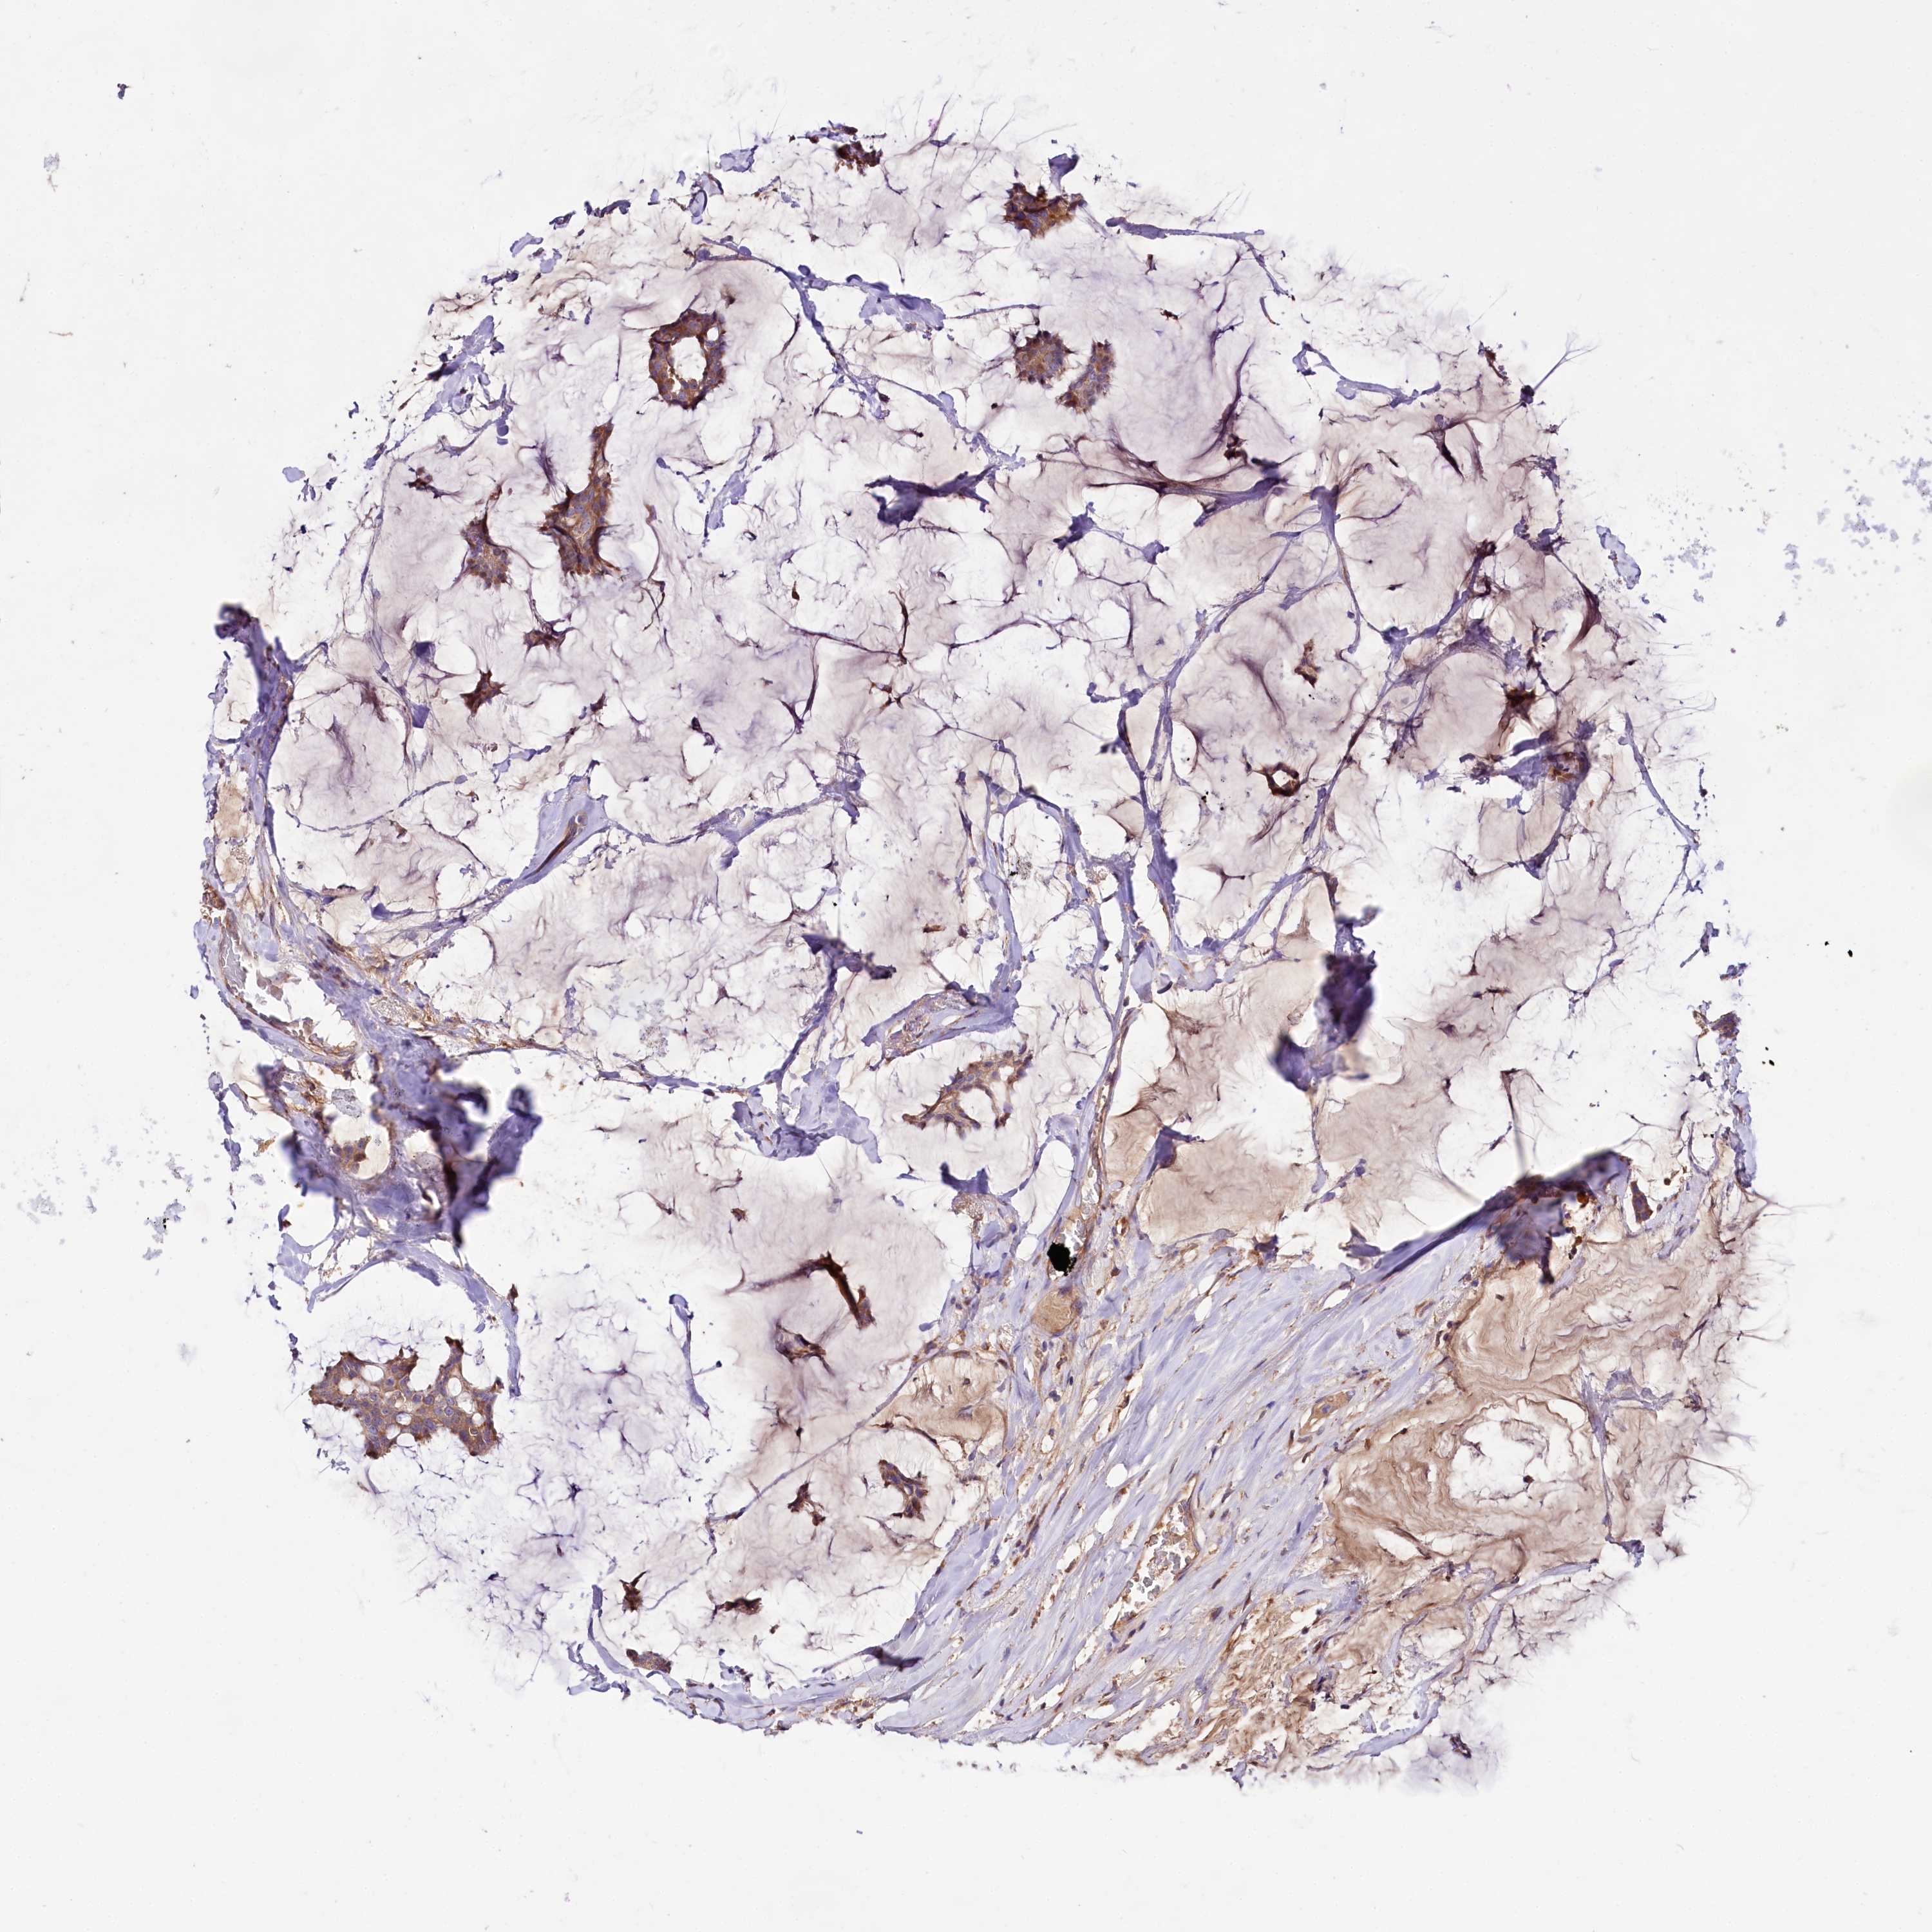

BRCA TCGA BRCA VALIDATION PROTEIN EXPRESSION

ANTIBODIES

AND

VALIDATION